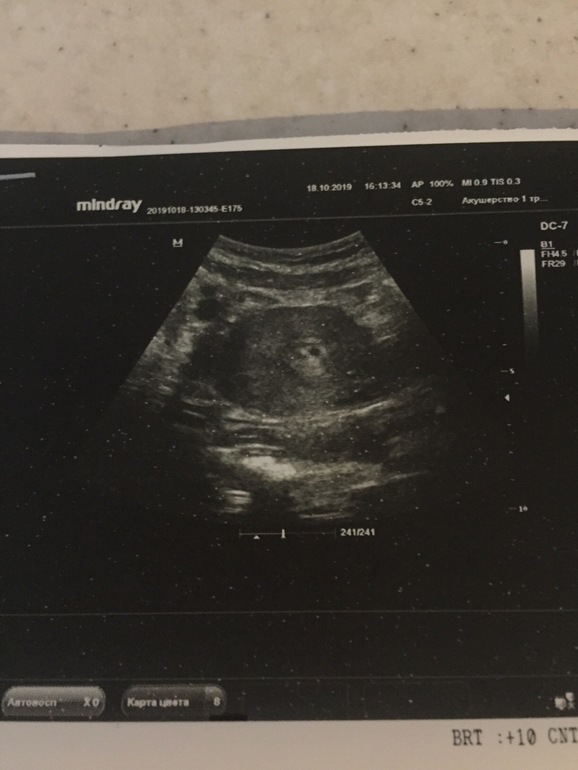

Яна Федорова 6 лет Гематома или двойня под вопросом Делали через брюшную стенку в частной клинике,пойду на второе узи,но очень переживаю..на что похоже? Посмотрите еще 20 записей на эту тему Отменить Ответить Чаты Беременных Выберите чат: Январята-2026 Февралята-2026 Мартята-2026 Апрелята-2026 Майчата-2026 Июнята-2026 Июлята-2026 Августята-2026